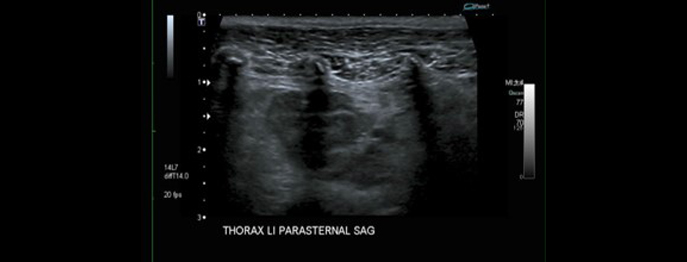

Ultraschalldiagnostik des Thorax

Nicht-kardiale Sonographie

In diesem vetinar werden wir uns mit der Bildgebenden Diagnostik von Thoraxveränderungen beschäftigen. Nach einer Erklärung der wichtigsten Punkte zum Ultraschall am Brustkorb und dem sogenannten T-FAST Schema werden einzelne anatomische Landmarken anhand von Fällen vorgestellt.

Spezielle Erkrankungen und deren Ultraschallbefunde werden unterstützt durch Informationen aus den Schnittbildverfahren anhand der Fallbeispiele demonstriert.

Abschliessend werden klassische Indikationen zur nicht-kardialen Sonographie am Thorax aufgezeigt